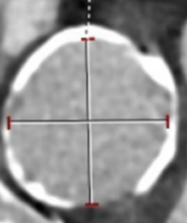

Imaging Corner

03/03/2024

Images/courtesy Semmelweis University, Budapest, Hungary

In this case, a 5’6”, 180 lb male patient with coronary artery disease was scanned on a photon-counting CT scanner (the NAEOTOM Alpha, Siemens Healthineers) for follow-up care after stenting and evaluation for in-stent restenosis.